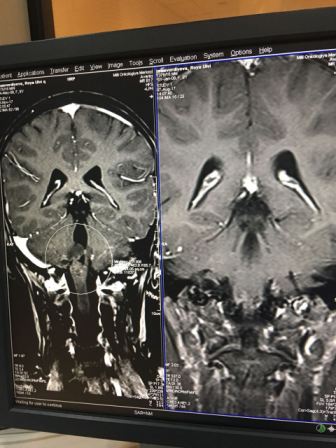

- Дочке сделали МРТ, пункцию, и результаты послали в Турцию, где врачи сказали, что необходимо срочно сделать Ройе операцию. Но на поездку в Турцию у нас нет денег, да и Ройа уже не в том состоянии, чтобы выдержать перелет. Сделать операцию нашей доченьке решился только один врач, доктор Вугар из Центральной клинической больницы. Он же провел Ройе первую операцию, которая была удачной. По его словам, только после операции будет ясно, что делать дальше. Потому что вероятно, что сейчас у Ройи – не опухоль, а просто скапливаемая жидкость дает такую картину. Возможно, предстоит еще долгое лечение. Но нам главное – спасти нашу Ройю, - плачет Вусаля ханум.

Ниже мы публикуем скрины медицинских документов, а также банковские реквизиты.